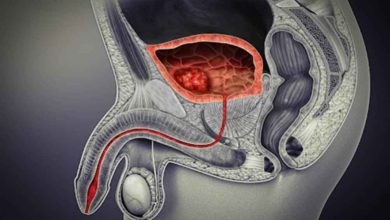

هل تضخم البروستاتا الحميد خطير؟ | احذر انسداد المثانة

إذا عانيت الأعراض الآتية، فدعني أخبرك باحتمالية إصابتك بتضخم البروستاتا الحميد. هل سبق أن عانيت صعوبة في أثناء التبول؟ أو…

تجربتي مع سرطان المثانة | الأعراض والأسباب والعلاج

سنسرد تجربة حالات شفيت من سرطان المثانة وأرادت توثيق رحلة المرض قائلة: خلال تجربتي مع سرطان المثانة عانيت بولًا دمويًا،…